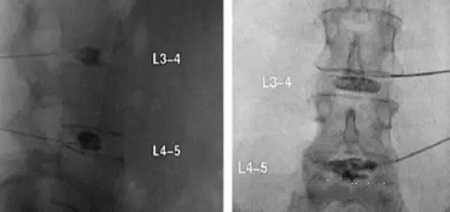

紐約spicial surgery 醫(yī)院的Gregory Lutz醫(yī)生報道了使用椎間盤內(nèi)PRP注射治療椎間盤退變的案例。患者是一位54歲的女性,嚴(yán)重的慢性腰痛,L4放射痛,L4-5椎間盤偏左側(cè)突出,接受過物理治療、非甾體類抗炎藥和介入治療,效果都不佳,2年后她接受了L3-4和L4-5椎間盤造影,發(fā)現(xiàn)L3-4正常,而L4-5誘發(fā)疼痛并發(fā)現(xiàn)纖維環(huán)裂隙?;颊呓邮芰薒4-5椎間盤內(nèi)注射PRP1.5ml治療,4周后疼痛幾乎完全緩解。18個月的隨訪疼痛和功能恢復(fù)非常滿意。

X線矢狀位和前后位L3-4和L4-5椎間盤造影術(shù)